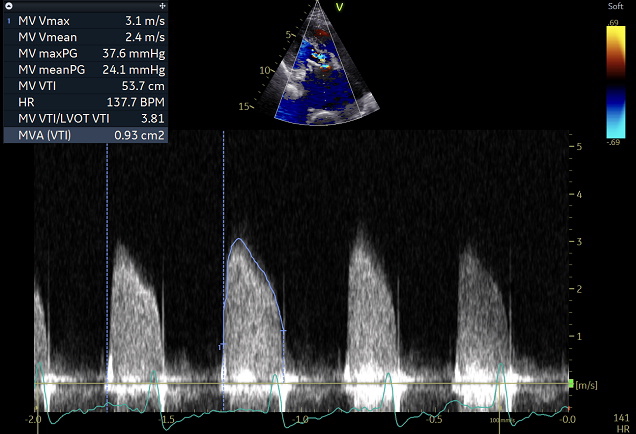

17年前に重症僧帽弁逆流症に対して生体弁置換術を行った症例。最近、労作時息切れを認めている。胸部聴診ではⅠ音亢進とⅡ音から遅れて始まる低調な拡張期雑音(拡張期ランブル)を聴取した。明らかな僧帽弁開放音は聴取しない。軽度の収縮期逆流性雑音も聴取する。(再生はイヤホンかヘッドホンを使用してください)

安静時の拡張期の僧帽弁平均圧格差は8.8mmHgで定義では中等度僧帽弁狭窄症となる

しかし労作時息切れが進行しているためエルゴメーター負荷心エコーを行った

運動中の拡張期僧帽弁平均圧格差は24mmHgと著明に上昇し、収縮期肺動脈圧65mmHgと肺高血圧を認めたため再弁置換手術となった。術後は労作時息切れが消失した。